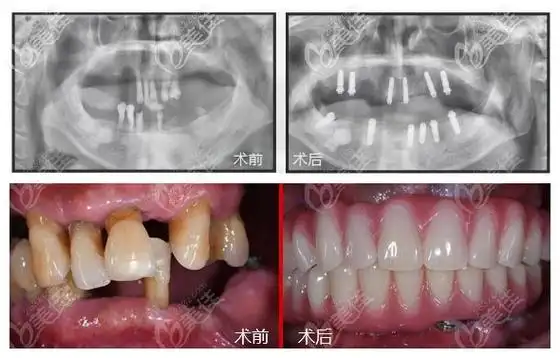

45岁就做德国icx上半口种植牙价格和恢复效果真的都不后悔